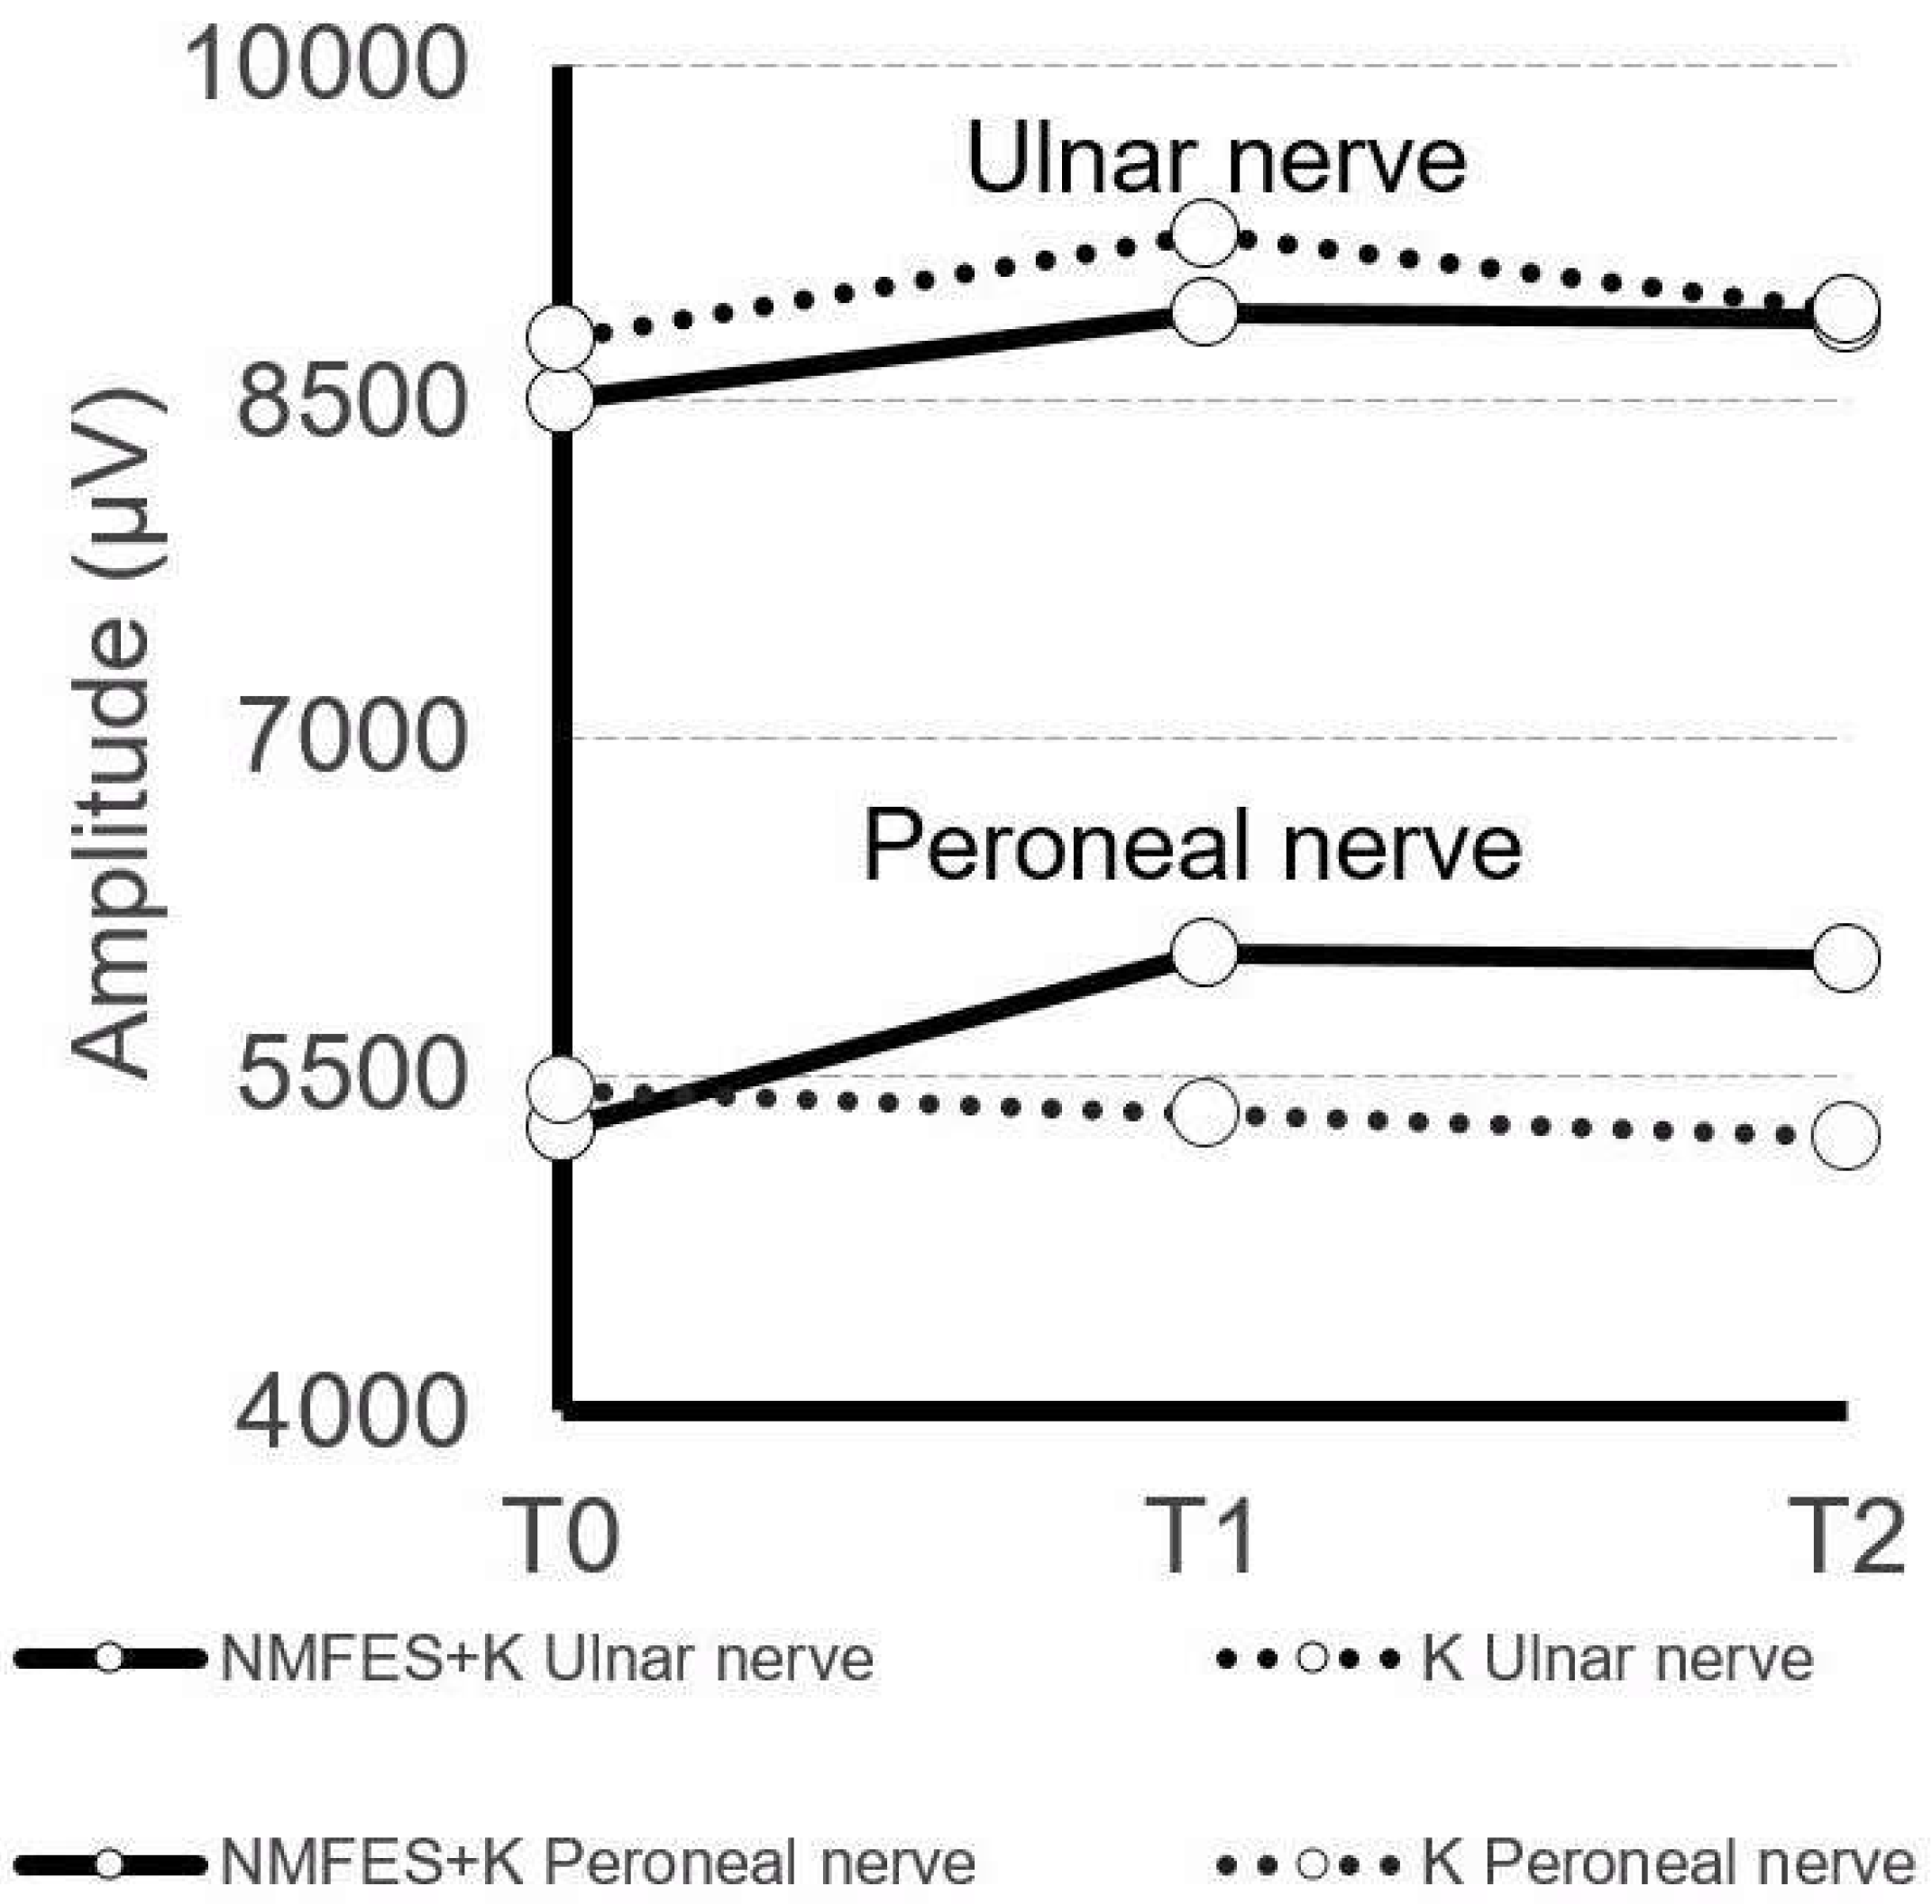

3. Results

| Ulnar nerve Amplitude (µV) | 9533 ± 2009 | 8580 ± 2227 | 8783 ± 2127 | 8809 ± 2122 | 9240 ± 2324 | 8872 ± 1175 | 8905 ± 2126 | NMFES+K NS K NS | NMFES+K p = 0.05 K NS | NMFES+K NS K NS |

| Peroneal nerve Amplitude (µV) | 8677 ± 1122 | 5268 ± 1211 | 5432 ± 1125 | 6035 ± 1225 | 5321 ± 1028 | 6009 ± 928 | 5224 ± 1005 | NMFES+K p = 0.04 K NS | NMFES+K p = 0.04 K p = 0.04 | NMFES+K p = 0.04 K p = 0.04 |